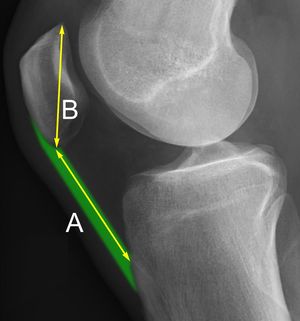

''슬개골 고위증(patella alta)''은 높이 위치한 무릎뼈를 의미한다. 약화된 슬개골 고위증(attenuated patella alta)은 관절 위에서 발달하는 비정상적으로 작은 무릎뼈이다.''슬개골 저위증(patella baja)''은 낮게 위치한 무릎뼈를 의미한다. 장기간 지속된 슬개골 저위증은 신전 기능 부전을 초래할 수 있다.[5]

''인설-살바티 비율''은 측면 X-ray에서 슬개골 저위증을 나타내는 데 도움이 되며, 슬개건의 길이를 슬개골의 길이로 나누어 계산한다. 인설-살바티 비율이 0.8보다 작으면 슬개골 저위증을 나타낸다.[6]